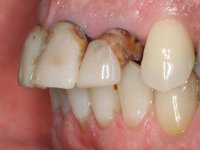

Patient male, 60 years old, non-smoker. After imaging and clinical examination, it was found that the patient had teeth 2.1 and 2.2 with extensive acrylic restorations, with screwed intra radicular posts and very poor endodontic treatments. Tooth 2.2 had an extensive apical lesion, the post had been placed on a false route and had mobility. Tooth 1.1 had an extensive resine restoration and tooth 1.2 presented a mesial restoration, also in composite resin, Class III type. The antero-superior sector was vestibularized, as consequence of a loss of vertical occlusion dimension associated with posterior edentulism. The patient showed reasonable periodontal health and satisfactory oral hygiene.